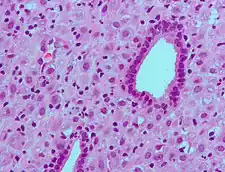

Micrograph showing changes to the endometrium due to progesterone (decidualization) H&E stain.

Progesterone has key effects via non-genomic signalling on human sperm as they migrate through the female tract before fertilization occurs, though the receptor(s) as yet remain unidentified.[43] Detailed characterisation of the events occurring in sperm in response to progesterone has elucidated certain events including intracellular calcium transients and maintained changes,[44] slow calcium oscillations,[45] now thought to possibly regulate motility.[46] It is produced by the ovaries.[47] Progesterone has also been shown to demonstrate effects on octopus spermatozoa.[48]